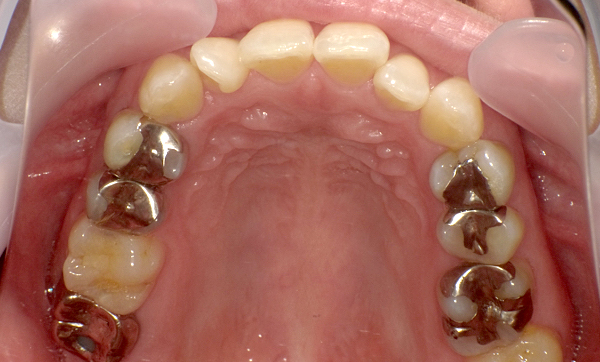

症例_008 「上下の前歯」症例

治療期間:13ヶ月金額:57万円+税40代女性捻転歯前歯のガタガタ

Before | After |